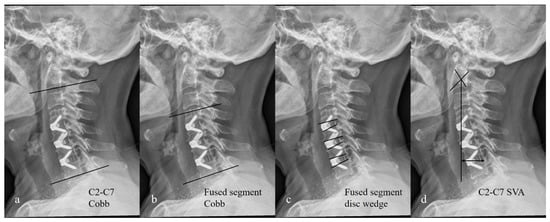

| C2-C7 Cobb (°) | |||

| Preop | 10.8 ± 8.1 | 11.1 ± 7.9 | 0.331 |

| Postop | 15.7 ± 7.4 | 24.8 ± 8.1 | 0.011 |

| Last FU | 12.5 ± 5.7 | 18.6 ± 6.9 | 0.023 |

| Fused segment Cobb (°) | |||

| Preop | 6.1 ± 6.8 | 5.9 ± 7.9 | 0.667 |

| Postop | 12.4 ± 7.1 | 19.8 ± 8.2 | 0.014 |

| Last FU | 9.5 ± 6.6 | 13.9 ± 7.4 | 0.025 |

| Fused segment disc wedge (°) | |||

| Preop | 5.8 ± 5.1 | 6.1 ± 6.9 | 0.564 |

| Postop | 11.3 ± 7.2 | 18.1 ± 7.9 | 0.012 |

| Last FU | 8.1 ± 6.8 | 13.6 ± 7.5 | 0.021 |

| C2-C7 SVA (mm) | |||

| Preop | 28.4 ± 11.3 | 30.1 ± 14.4 | 0.248 |

| Postop | 30.2 ± 14.6 | 28.2 ± 15.7 | 0.145 |

| Last FU | 31.7 ± 13.9 | 29.6 ± 16.5 | 0.233 |